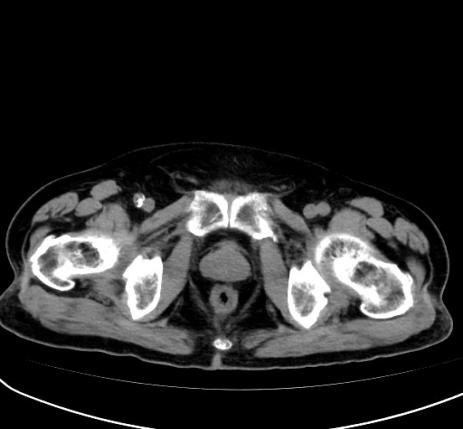

2024年12月,患者因腰痛来院,查CT(图12):右肺上叶癌粒子植入表现,左肺上叶转移治疗期表现,COPD并左肺下叶纤维灶,左侧肾上腺结节较前未见变化,T11椎体及左侧附件、骶1-2椎体骨质破坏,考虑转移瘤。

2024年12月,复查提示疾病进展,骶椎转移,予以骶椎转移灶姑息性放疗1个疗程,PTV(低1、2椎体转移灶,30Gy/10f/3.0Gy),并予“伊班磷酸钠6mgd1-3”抗骨质破坏治疗。经治疗,患者主观感受为骶椎周围异样感觉消失,麻木、感觉迟钝消失,疼痛感消失,病情好转。